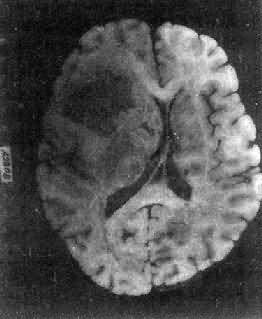

图16-23 星形胶质细胞瘤 左大脑半球肿胀,肿瘤边界不清,部分呈胶冻状 镜下,肿瘤细胞形态多样,可相似于纤维型星形胶质细胞、原浆型星形胶质细胞和肥胖星形胶质细胞,故分别称为纤维型、原浆型和肥胖型星形胶质细胞瘤。前二者为良性肿瘤,后者性质介于良恶性之间。如肿瘤细胞出现间变,细胞密度增大,异型性明显,核深染,出现核分裂像,毛细血管内皮细胞增生,则为间变性星形胶质细胞瘤,为恶性肿瘤。 高度恶性的星形胶质细胞瘤称为多形性胶质母细胞瘤(glioblastoma multiforme),多见于成人。肿瘤好发于额叶、颞叶白质,浸润范围广,常可穿过胼胝体到对侧,呈蝴蝶状生长(图16-24)。瘤体因常有出血坏死而呈红褐色。镜下,细胞密集,异型性明显,可见怪异的单核或多核瘤巨细胞。出血坏死明显,是其区别于间变性星形胶质细胞瘤的特征。毛细血管明显增生,内皮细胞增生、肿大,可导致管腔闭塞和血栓形成。肿瘤发展迅速,预后极差,患者多在2年内死亡。